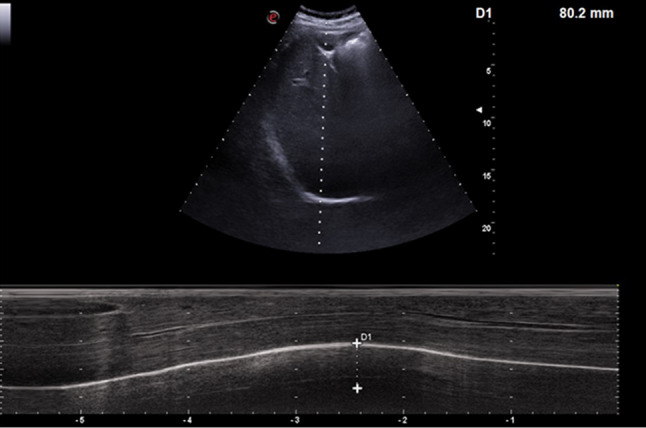

The patient was subsequently referred for pneumological counseling. Respiratory function tests showed a severe restrictive alteration (Fig. 3), and the completion with high-resolution computed tomography allowed to diagnose an idiopathic pulmonary fibrosis (IPF) (Fig. 4).

Fig. 4.

High-resolution computed tomography (HRCT) examination revealed findings suggestive for idiopathic pulmonary fibrosis (IPF): architectural distortion, reticulation, and honeycombing involving mainly the lung periphery and the lower lobes